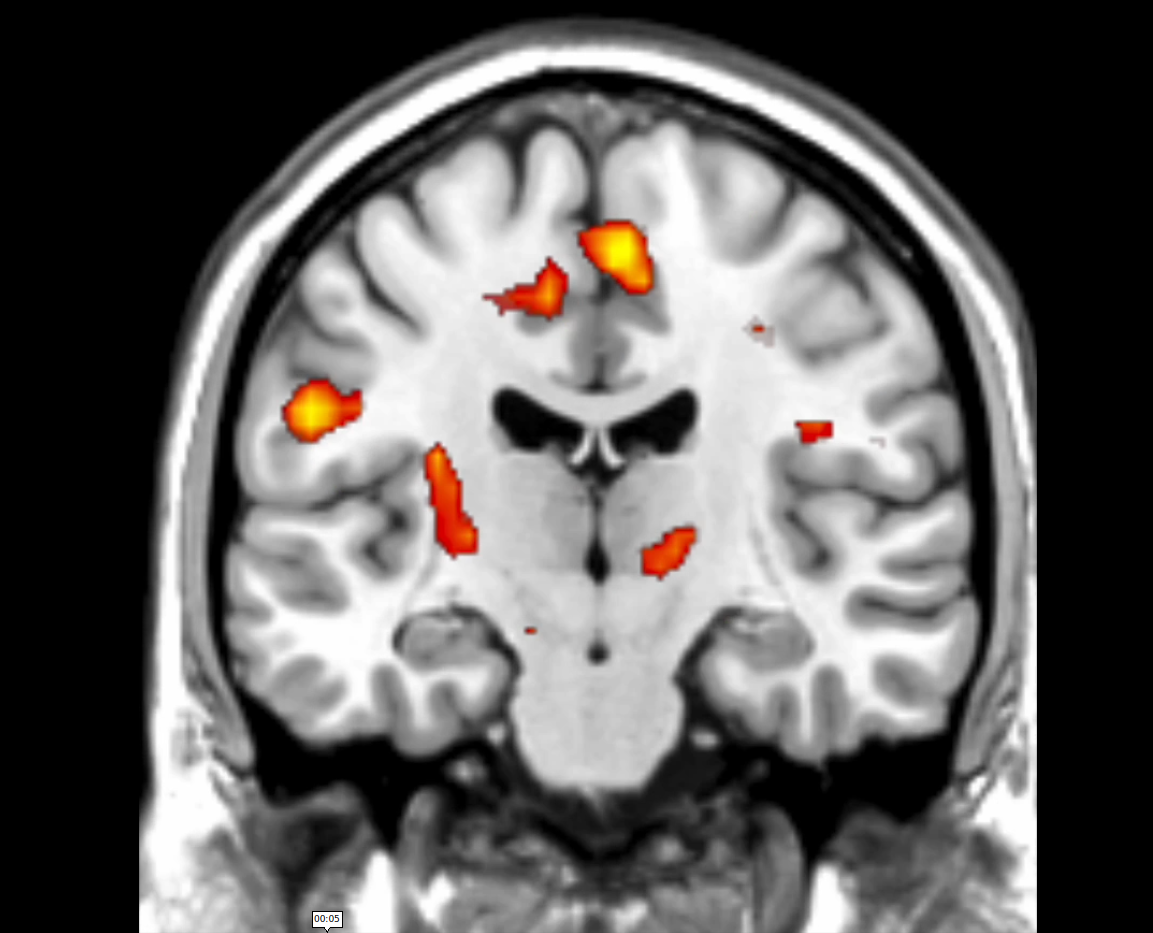

We look at how key regions (e.g., prefrontal cortex, striatum) support self-regulation, especially under the influence of reward and emotion. We also develop models to understand how people learn and control stimulus-response associations, and examine cases where cognitive control fails, such as in impulsivity and brain lesions.

In disorders like addiction and impulsivity, habitual actions and cognitive control go awry, leading to excessive or compulsive behaviors. Focusing on addiction, impulse control disorders, and Parkinson's disease, we aim to uncover the neural changes that drive these behaviors and explore new treatment strategies.